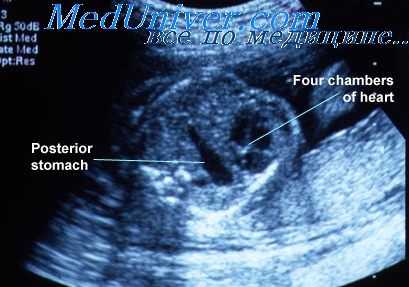

Эхографическая картина у плодов с мекониальным перитонитом бывает различной. Полагают, что наиболее характерной ультразвуковой находкой в этих случаях являются кальцинаты, локализованные в брюшной полости. Механизм их образования заключается в том, что меконий, попавший в брюшную полость вызывает развитие асептической воспалительной реакции, что стимулирует образование фиброзных спаек, которые затем кальцинируются.

Кальцинаты характеризуются высокой эхогенностью и могут иметь точечную линейную форму или группироваться в более крупные включения. В связи с небольшими размерами кальцинатов эффект «акустической тени» может не всегда визуализироваться позади них.

Иногда процесс образования кальцинатов может распространяться и в полость грудной клетки через постоянно сформированные отверстия диафрагмы (для нижней полой вены, пищевода или аорты) или через временно открытые отверстия (левый и правый плевроперитонеальный каналы, отверстие Morgagni).

Несмотря на то что интраабдоминальные кальцинаты считаются типичными для мекониального перитонита, их обнаружение в брюшной полости плода не обязательно будет свидетельствовать о наличии этого осложнения. Другие возможные причины появления таких кальцинатов включают в себя кальциноз печени и селезенки (при некрозе печени; идиопатическом кальцинозе и внутриутробной инфекции, например при цитомегалии или токсоплазмозе), образование кальцинатов в структуре опухолей (при тератоме или нейробластоме) или возникновение кальцинатов в просвете кишки у плодов с атрезией ануса.

Мекониальный перитонит можно отличить от перитонита другой этиологии, если кальцинаты распределены по брюшине. Однако в связи с тем, что печень занимает значительную часть объема брюшной полости у плода, иногда бывает затруднительно точно оценить локализацию кальцинатов: в печени или на поверхности висцеральной брюшины. Тем не менее существует несколько эхографических маркеров, которые будут свидетельствовать об их перитонеальном расположении: точечные гиперэхогенные фокусы определяются только за предполагаемыми границами печени и не визуализируются в ее паренхиме, кальцинаты доходят до диафрагмы и образуют скопления на ее брюшной поверхности, а также визуализируются в мошонке плода мужского пола.

Наличие кальцинатов в мошонке является особенно демонстративным признаком поскольку влагалищный отросток брюшины соединяет полость мошонки с перитонеальной полостью на поздних сроках беременности.

У плодов с мекониевым перитонитом также может наблюдаться ряд других эхографических признаков. Они включают в себя многоводие, расширенные петли кишечника, асцит, гиперэхогенный асцит с наложением фибриновых масс на поверхности органов брюшной полости плода, наличие паховой грыжи и мекониальных псевдокист.

Паховые грыжи, выявляемые в антенатальном периоде, по данным литературы могут обнаруживаться как при мекониальном перитоние, так и быть изолированной находкой. Мекониальная псевдокиста представляет собой отграниченную полость, сформированную из кишечного содержимого, попавшего в брюшную полость, которое окружено соединительно-тканной капсулой и спаянными между собой петлями кишечника.

При ультразвуковом исследовании мекониальные псевдокисты имеют вид кистозных структур неправильной формы с утолщенными стенками, локализованных в брюшной полости плода, в просвете которых может определяться детрит, перегородки, кальцинаты или все перечисленное. Однако источник образования таких кист может оставаться не выявлен, поскольку дифференциальный ряд при оценке кистозных образований в брюшной полости плода достаточно широк и включает в себя мегацистис, кисту яичника, кисты при дупликациях ЖКТ, тератому, мезентериальную кисту, кисту холедоха и гидрометрокольпос. Тем не менее если кальцинаты в брюшной полости выявляются в сочетании с кистозным образованием смешанной эхоструктуры, с достаточной долей уверенности может быть установлен диагноз мекониального перитонита с образованием мекониальной псевдокисты.